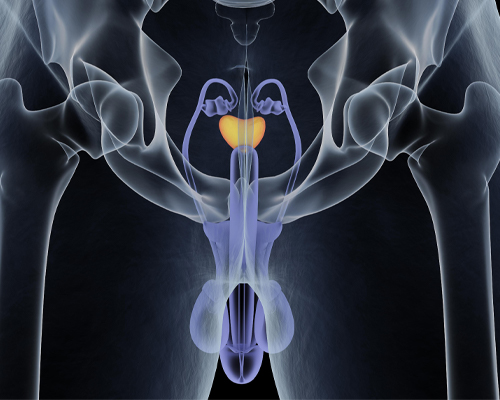

He had extensive and grounded training in dealing with management of patients with kidney stone disease, urological malignancies, male sexual dysfunction, urethral stricture disease, prostate related disease and Renal transplant. His training also includes management of simple and complicated UTI, Urosepsis, Neurogenic Bladder, OAB, UAB, Renal Trauma, urinary incontinence, female Urology, Bladder pain syndrome.